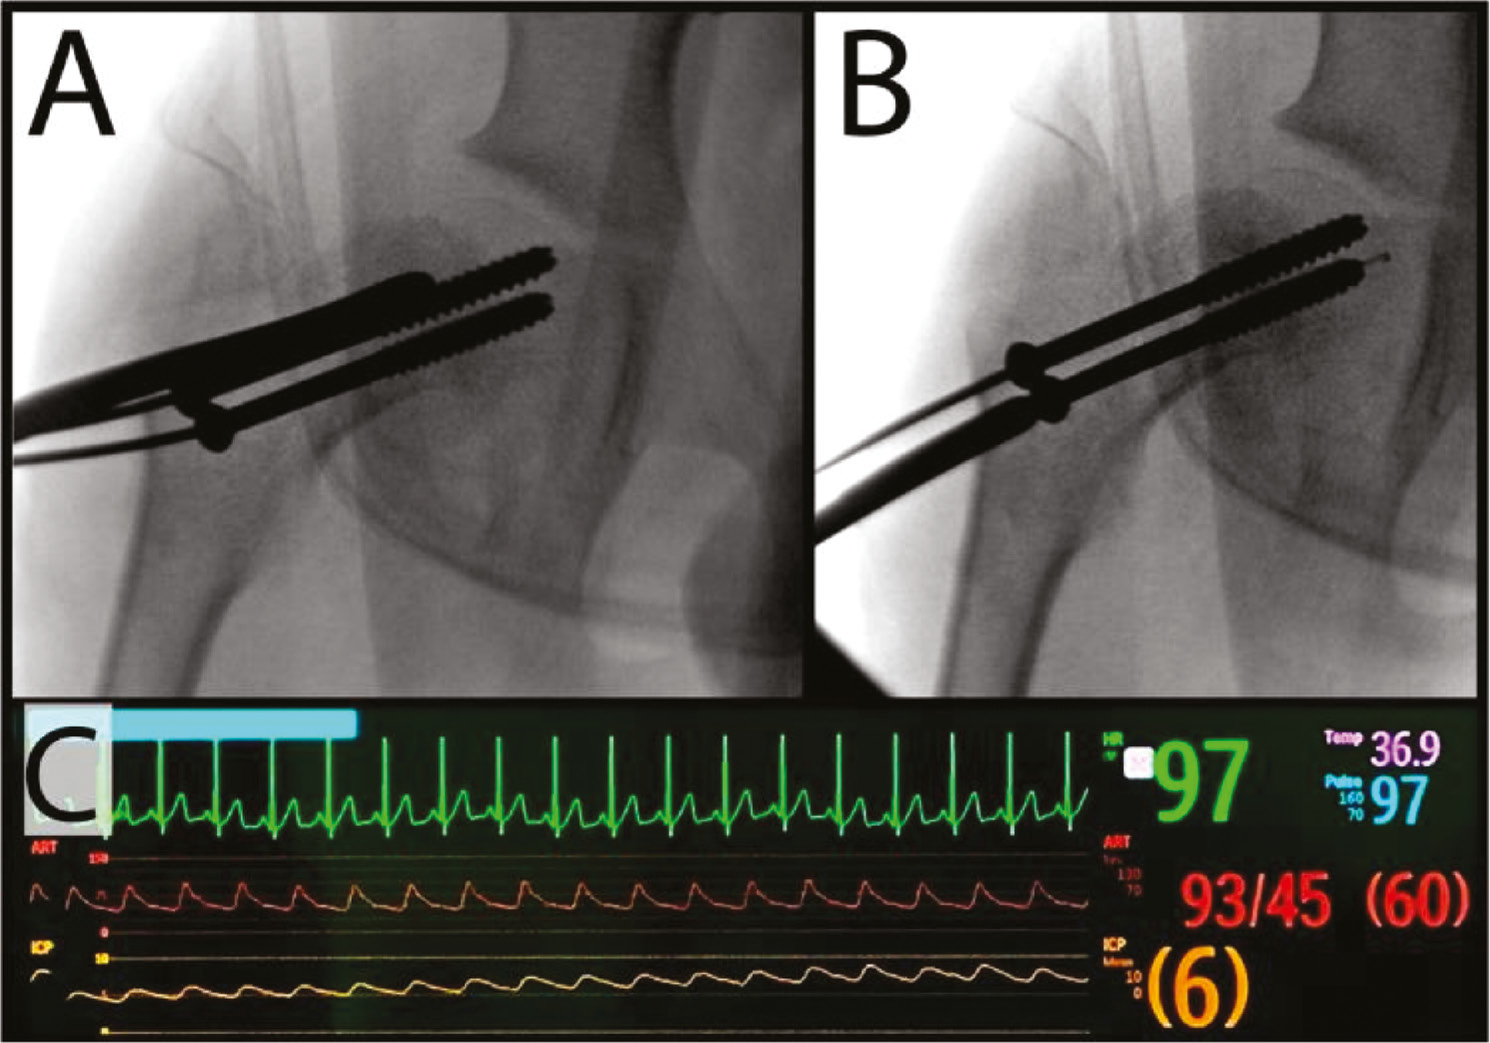

Typical radiographic evaluation of SCFE identifies characteristic findings reflective of displacement of the epiphysis, including widening of the physis when compared to the contralateral side, relative posterior displacement of the epiphysis on the frog lateral, and apparent decreased epiphyseal height (due to posterior displacement).39 Historically, Klein’s line has been utilized in the diagnosis of SCFE on plain radiographs. Using the anterior-posterior (AP) view, a line is drawn tangent and parallel to the superior surface of the femoral neck through the epiphysis. In normal hips, this line should intersect the epiphysis. In SCFE, this line intersects less or completely misses the epiphysis and is diagnostic of SCFE (Figure 2).5,39

Figure 2. Anterior-posterior (AP) and frog lateral radiographs of an 11-year-old male with stable right SCFE. (A) AP view demonstrates that Klein’s line, a line parallel to the femoral neck at its superior border (white dashed line), intersects less epiphysis on the right, affected side. (B) Frog lateral view demonstrates physeal widening and relative posterior displacement of the right capital femoral epiphysis on the metaphysis.

jposna2022589_fig2.jpg

More recent literature however suggests that Klein’s line is not sensitive enough to detect all slips and should not be over-relied upon, specifically in the case of mild slips or hips in a pre-slip phase. Green et al.40 proposed a modified Klein’s line, in which a similar line was drawn on the contralateral hip and a difference of 2 mm suggests a possible slip with greater sensitivity.